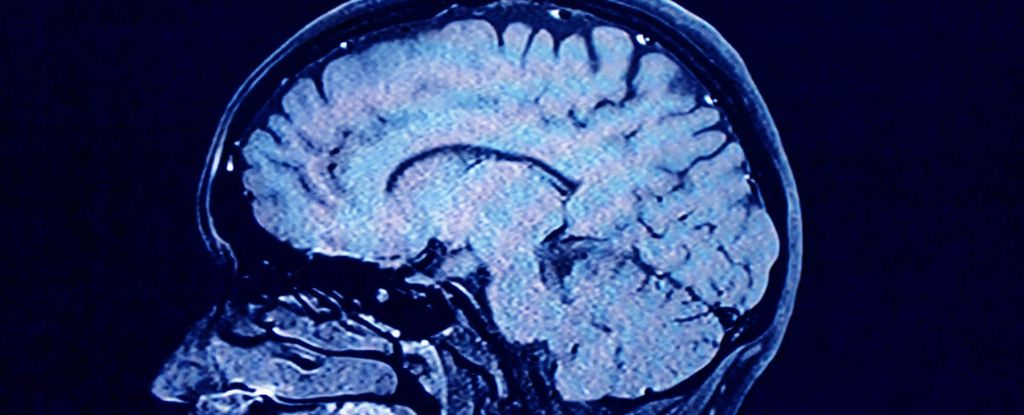

Viral Infections and Their Potential Role in Alzheimer's Disease

Research suggests that the herpes simplex virus type 1, which causes cold sores, may play a significant role in the development of Alzheimer's disease by reactivating in the brain and causing damage, especially in individuals with certain genetic risk factors. Preventative measures like vaccines and antiviral treatments could potentially reduce the risk of Alzheimer's.